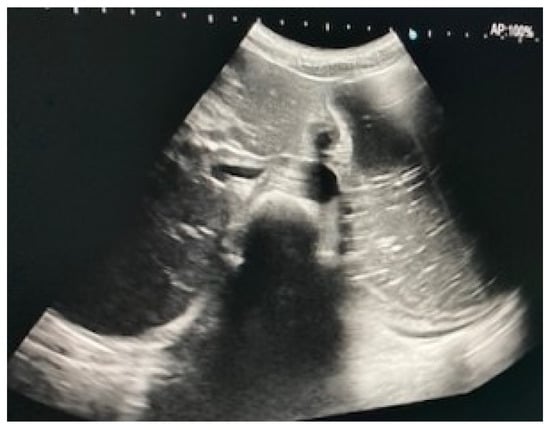

Immediate exploration of the abdomen was performed in the Emergency Department using X-rays, ultrasound, and a computed tomography (CT) scan of the abdomen. The abdominal ultrasound revealed an enlarged stomach (Figure 2), and the CT showed a vascular abnormality with a reduction of the aorto-mesenteric space of 21.6° and a distance (3.54 mm) obstructing the third portion of the duodenum, and partial left renal vein stenosis confirming the diagnosis of SMAS and Nutcracker syndrome (Figure 3).

Figure 2.

Abdominal ultrasound showing gastric distension.